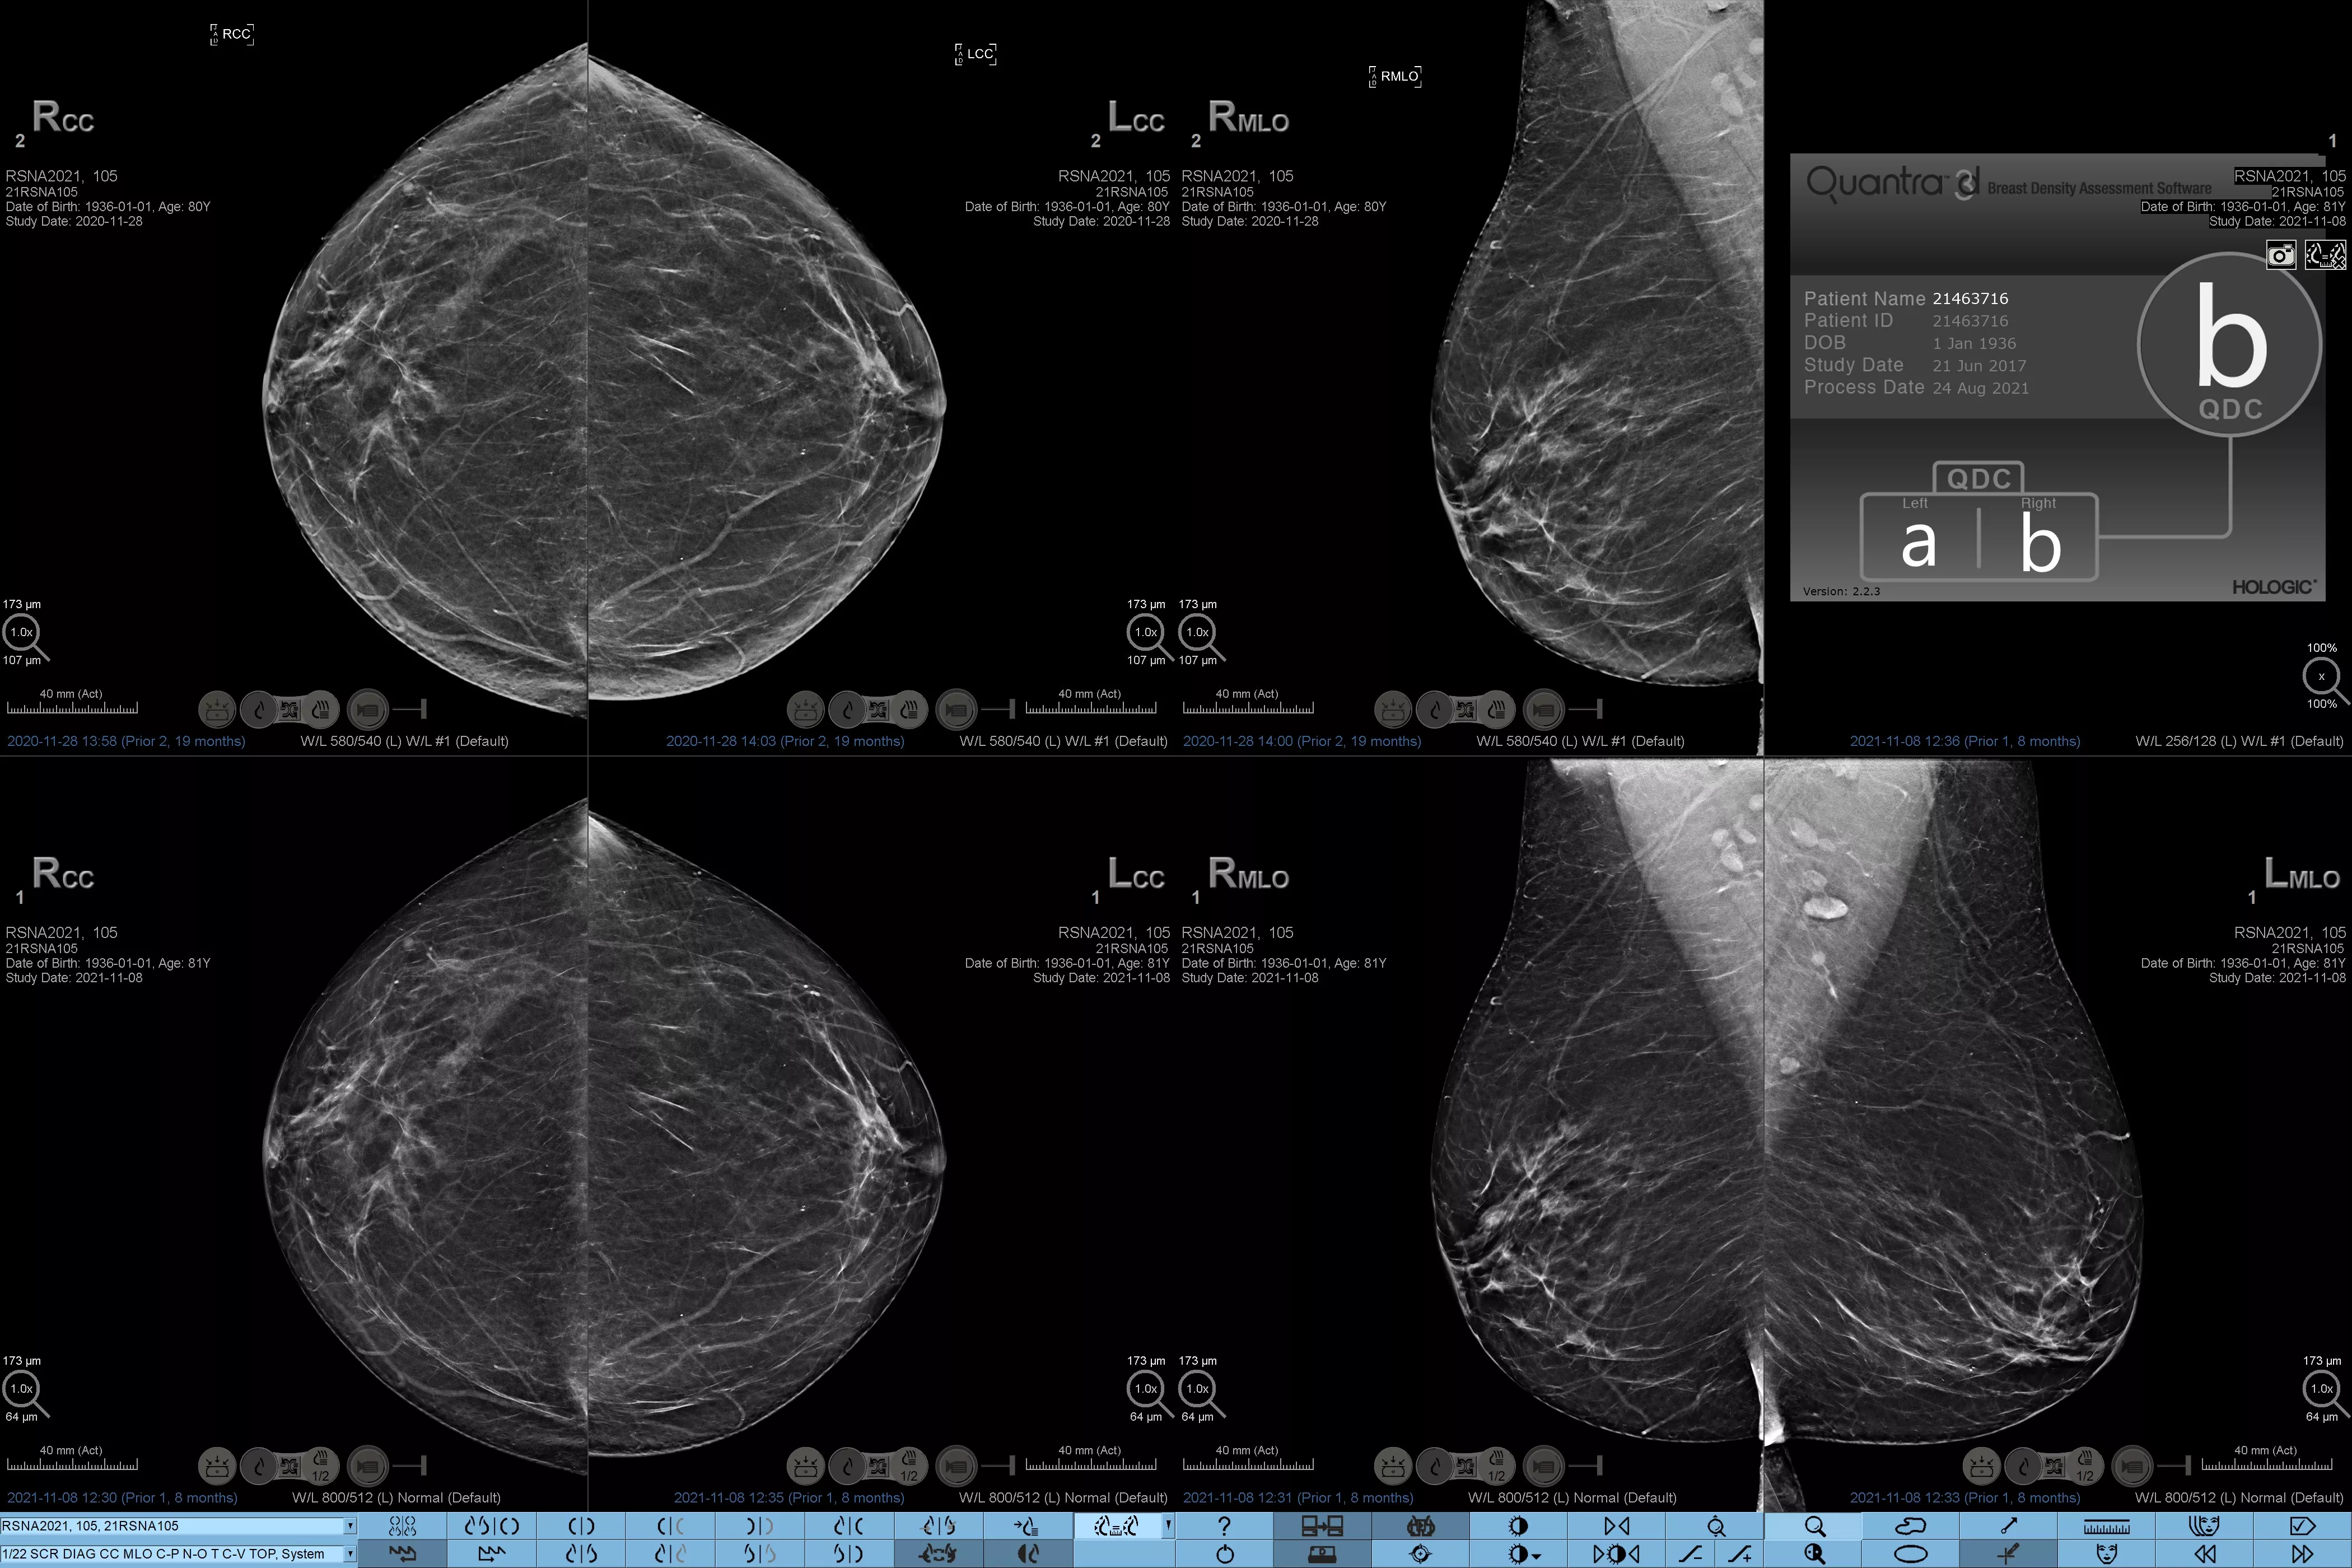

Higher breast density is known to increase a woman’s risk for breast cancer.1 The need for accurate, unbiased analysis is therefore critical. Powered by machine learning, Quantra technology software analyses both 2D™ and tomosynthesis images for distribution and texture of parenchymal tissue. It categorises breasts in four breast composition categories consistent with guidance from the American College of Radiology (ACR) BI-RADS Atlas 5th Edition.2

Objective machine learning algorithm that assigns breast density category based on analysis of breast tissue texture and patterns.

• Overcoming subjectivity in visual assessment, providing more consistent, and more reliable scoring.*

*Scores are based on ACR BI-RADS categories, in line with the revised guidance by the American College of Radiation (ACR) BI-RADS Atlas 5th Edition. This accounts for pattern and texture, compared with volume, when determining density.